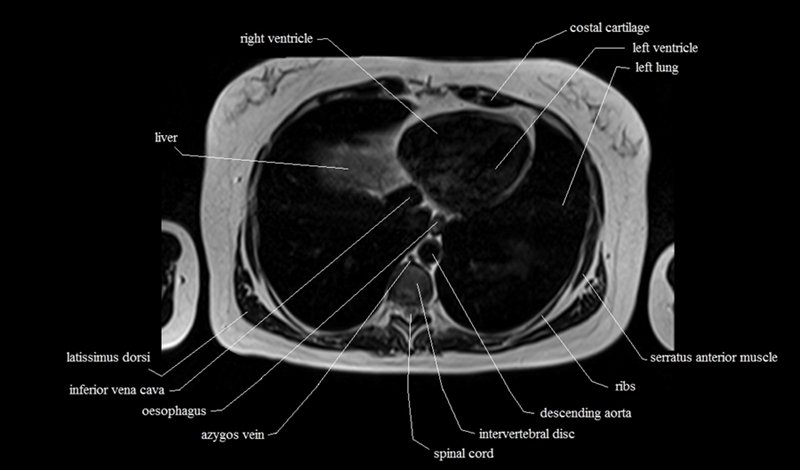

MRI Axial Cross Sectional Anatomy of Chest

This MRI chest (thorax) axial cross sectional anatomy tool is absolutely free to use. Use the mouse scroll wheel to move the images up and down, or alternatively, use the tiny arrows (→) on both sides of the image to navigate through the images. For a more detailed view, double-click the image to view it in full screen, and use the menu in the top right-hand corner to view individual slides or play them in a loop.